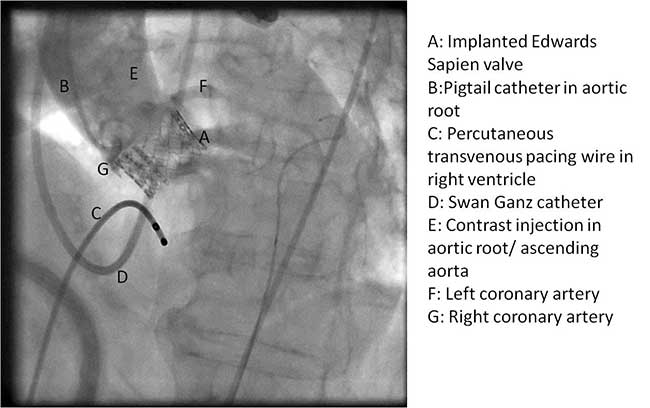

The Sapien valve is a balloon expandable platform and it comes in two sizes, 23 mm and 26 mm. The valve is prepared and mounted onto a sheath system for implantation on the back table. The femoral arterial access is serially dilated to accommodate a 22 French (for 23 mm Sapien valve) or a 24 French (for 26 mm Sapien valve) sheath. The balloon mounted valve is then advanced in a retrograde fashion into the aortic valve position using angiographic and echocardiographic guidance (Figure 2). It is important to visualize the position of the valve using at least 2 different angles. For the transfemoral approach, the recommended positioning of the prosthesis is 60%-40%, which is 60% of the prosthesis should be on the ventricular side of the aortic annulus with 40% of the prosthesis on the aortic side of annulus. This is due to the past experience observation that the prosthesis has a tendency to migrate in the aortic direction during deployment. This phenomenon is likely a result of the stored torque in the delivery system when introduced from the femoral artery. For ease of prosthesis arch transit, the delivery platform is equipped with the Retroflex system from Edwards. Of note, the correct orientation of the prosthesis should be confirmed both visually prior to placement into the introducer sheath and angiographically prior to deployment. Next, transvalvular flow is severely depressed by rapid ventricular pacing. The valve is then balloon expanded rapidly and implanted in position. If there is moderate to severe aortic insufficiency from a paravalvular leak after the deployment, a second ballooning with a larger volume is performed under conditions of rapid ventricular pacing.

After valve implantation, it is critical to confirm valve competence, visualize coronary flow, and check for aortic injury by performing echocardiography and completion angiography (Figure 3). In the stabilized patient, the large femoral sheath is removed while maintaining wire access, ensuring no damage to the iliac artery. Once flow is confirmed in the proximal and distal femoral artery, the guidewire can be removed. The artery is clamped on either side and the arteriotomy is closed primarily with interrupted 5-0 or 6-0 prolene. The incision site is closed in standard fashion with absorbable suture in layers. The femoral arterial and venous sheaths in the contralateral groin may be left in place and then removed when the activated clotting time reverses to normal. Patient is taken back to the cardiothoracic intensive care unit for postoperative recovery.